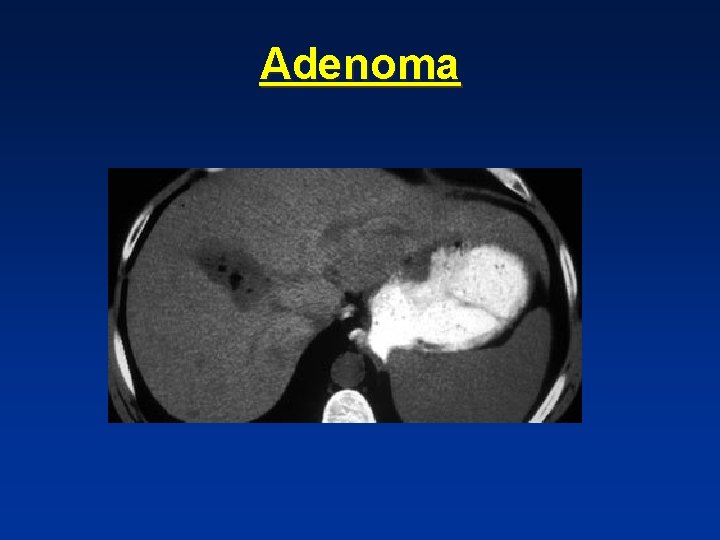

Adenoma

• Best diagnostic clue: spherical well defined hypervascular and heterogenous mass due to fat & hemorrhage. • Symptomatic in 80%-abdominal pain- ( FNH asymptomatic in 80%) • 98% in yoyung females taking oral contraceptives • Not seen in males unless on anabolic steroids or with glycogen storage disease.

• Adenoma showing capsule in delayed phase

• Female with acute abdominal pain • On portal phase, hypodense hepatic lesion with hemorrhage adjacent to it, extending subcapsularly.

• Fat in adenom a

• Hemorrhage in adenoma

Capsule • Hepatocellular carcinoma “ HCC “ • Adenoma • Biliary cystadenoma

Fat • Adenoma • HCC • Metastatic liposarcoma • Angiomyolipoma

Blood • HCC • Adenoma